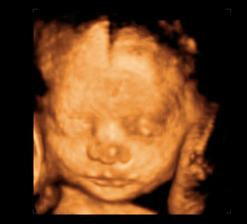

26 tt../1.4.2009/ naša paulínka je stráášne zlatá, boli sme si pozrieť na 4D utz. ..tvárila sa veľmi dôležito, až nafúkano...hehe..vôbec sa nechcela usmievať... nakoniec sa nám aj zasmiala...v brušku veľmi vyvádza, maminke dosť vytláča všetky časti telíčka, čo je niekedy aj dosť bolestivé...ale vydržíme, drobečkovi je tam určite tiež pritesno..a ešte aj stále viac a viac bude... strááášne sa na ňu tešíme🙂))